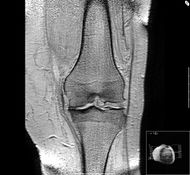

إن الفصال العظمي يتم تشخيصه إكلينيكيا ومن الممكن أن يتم إثباته عن طريق التصوير بالأشعة السينية ومن المهم أن نتذكر أن هناك علاقة ضعيفة بين الملامح الإكلينيكية والملامح الشعاعية ومن المنظور البحثي تتم الآن دراسة عدد كبير من الواسمات الكيميائية الحيوية وتقنيات التصوير الشعاعي لكي يتم تقييم الفصال العظمي بدقة وقد تم استخدام تقنيات التصوير مثل فائق الصوت والأشعة السينية المكبرة والتصوير بالأشعة الومضانية (Scintigraphy) لكي تعطى صورة أفضل للغضروف وما تحته من عظام ويعطينا منظار المفصل المصغ ر وباستخدام منظار المفصل الرفيع الجديد للرؤية المباشرة لسطح الغضروف ومن الممكن في المستقبل أن يعطينا وسيلة لتقييم تقدم المرض ولكن لا توجد دواع في الوقت الراهن لاستخدام تقنيات التصوير هذه في التشخيص السريري.

ومن المفاصل الرئيسية الأخرى التي تتأثر بالفصال العظمي هي المفصل الأول بين سلاميات القدم ومفصل الفخذ والركبة. وهو ينتشر بدرجة خاصة في هذه المفاصل في كبار السن ولكن التنبؤ به مختلف ويعتمد على الجزء المصاب من المفصل وقد تكون الإصابة من ناحية واحدة أو ناحيتين. ويمكن تقسيم الفصال العظمي لمفصل الفخذ إلى مجموعات ثانوية (Subsets) هي علوي جانبي وإنسي وحلقي وكذلك يمكن تقسيم الفصال العظمي لمفصل الركبة إلى مرض القسم الإنسي الجانبي ومرض المفصل الظنبوبي الفخذي أو مرض المفصل الفخذي الرضفي وكل من هذه الحالات قد تتصرف بطريقة مختلفة من ناحية بداية المرض وتقدمه على الرغم من أن العملية المرضية هي نفسها. وقد تكون هناك إصابة سابقة لأعوام كثيرة مضت في حالة الفصال العظمي للركبة وقد تصاب بعض المفاصل الأخرى الكبيرة بالفصال العظمي بما فيها مفصل الكتف والكاحل ولكن لابد أن توضع بعض الأسباب الأخرى في الاعتبار إذا كانت هذه المفاصل هي البذرة الأساسية للمرض.